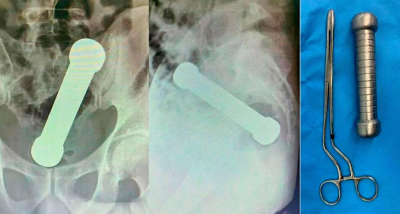

La víctima, de 54 años, se presentó en un hospital de la ciudad Manaos, noroeste de Brasil, con dolor abdominal, náuseas y dificultad para defecar. Le hicieron una radiografía que mostró que tenía un objeto de metal de 4,4 libras y casi 20 cm en el ano. Se calcula que la mancuerna estuvo alojada allí por lo menos dos días.

En primera instancia, los cirujanos intentaron extraerle el objeto usando pinzas, pero finalmente tuvieron que intervenirlo. La operación fue exitosa y fue dado de alta después de tres días sin complicaciones.